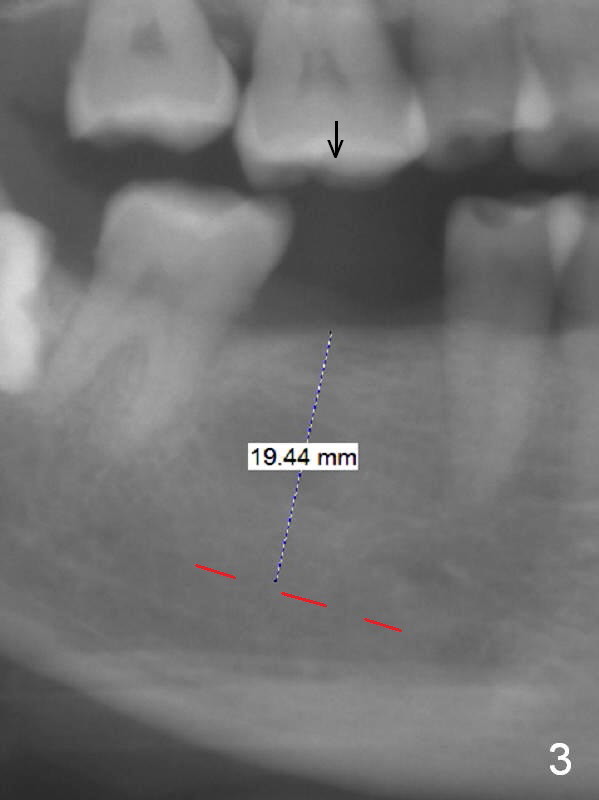

A 57-year-old woman has 3 missing molars, including #30 (Fig.1). Although she looks skinny, clinically the ridge is moderately wide. Magic Split will be used for access (flapless) and bone density testing. From PA, the bone density does not seem to be low (Fig.2). Use the 1.6 mm drill without stopper for further bone density testing. The initial depth will be 15 mm (gingival level, Fig.3). After PA confirmation of the trajectory, use 3.8 mm Magic Drill for 15 mm. Try 4.5x11 mm dummy implant, followed by PA. When an abutment is placed, trim the opposing surpraerupted tooth if necessary (Fig.3 arrow).